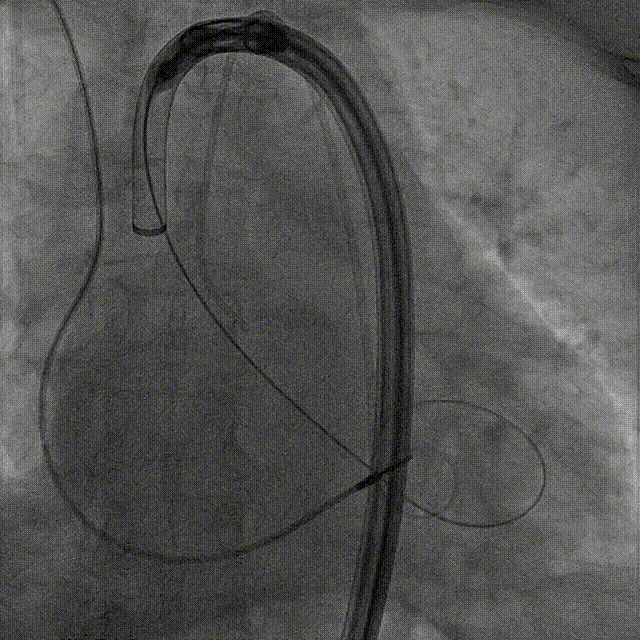

起搏一键释放

术后造影